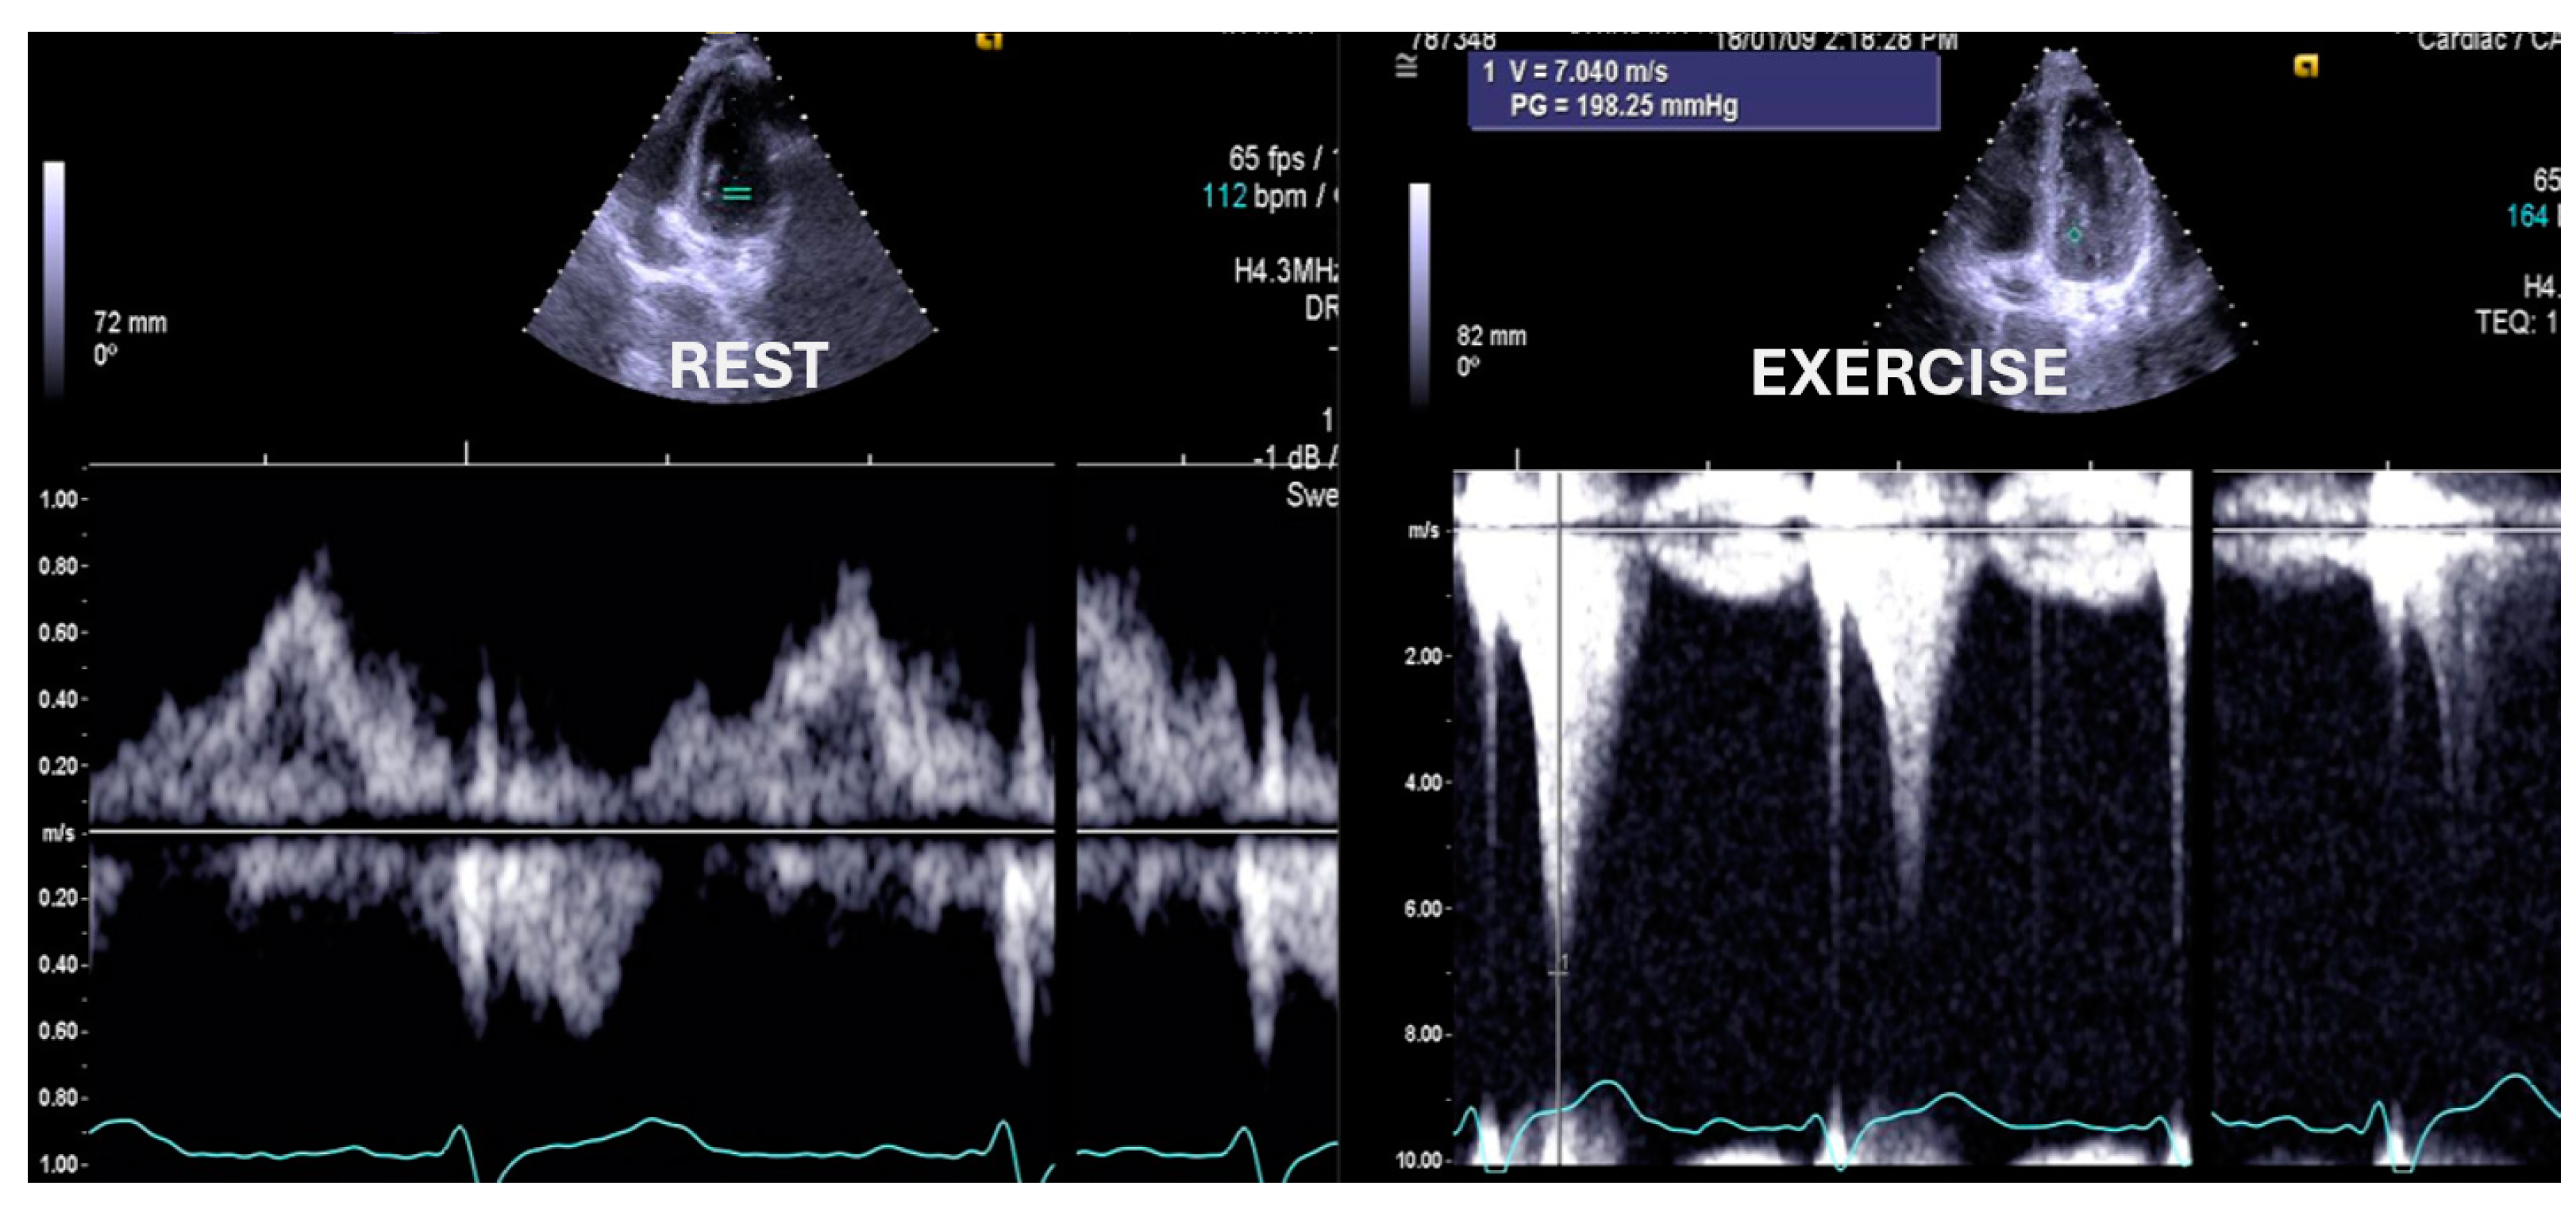

The ESEs for the 10 asymptomatic children whose screening was requested by their parents, 11 with symptoms unrelated to exercise, and 12 with antecedents of sudden death in the family showed normal results. The two children with previously intervened aortic coarctation revealed an increase in the aortic gradient, with reintervention required in one of them (Figure 7).

Figure 7.

Aortic gradient evaluated in a patient with aortic coarctation previously treated with a stent. Based on the exercise stress echocardiography results, the child was treated again [1].

The child with Cortriatriatum sinister revealed a nonsignificant increase in the diastolic mean gradient (Figure 8).

Figure 8.

The exercise Doppler data in conjunction with the exercise and clinical data led the medical team to keep the patient in close clinical follow-up. (A): Intra–atrial septum in “cortriatriatum”; (B): color flow before exercise; (C): color flow at peak exercise; (D): continuous–wave (CW) flow before exercise; (E): CW flow at peak exercise [1].